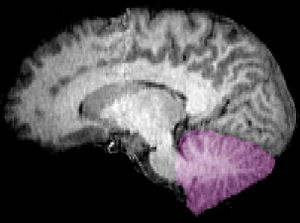

Cerebellum. |